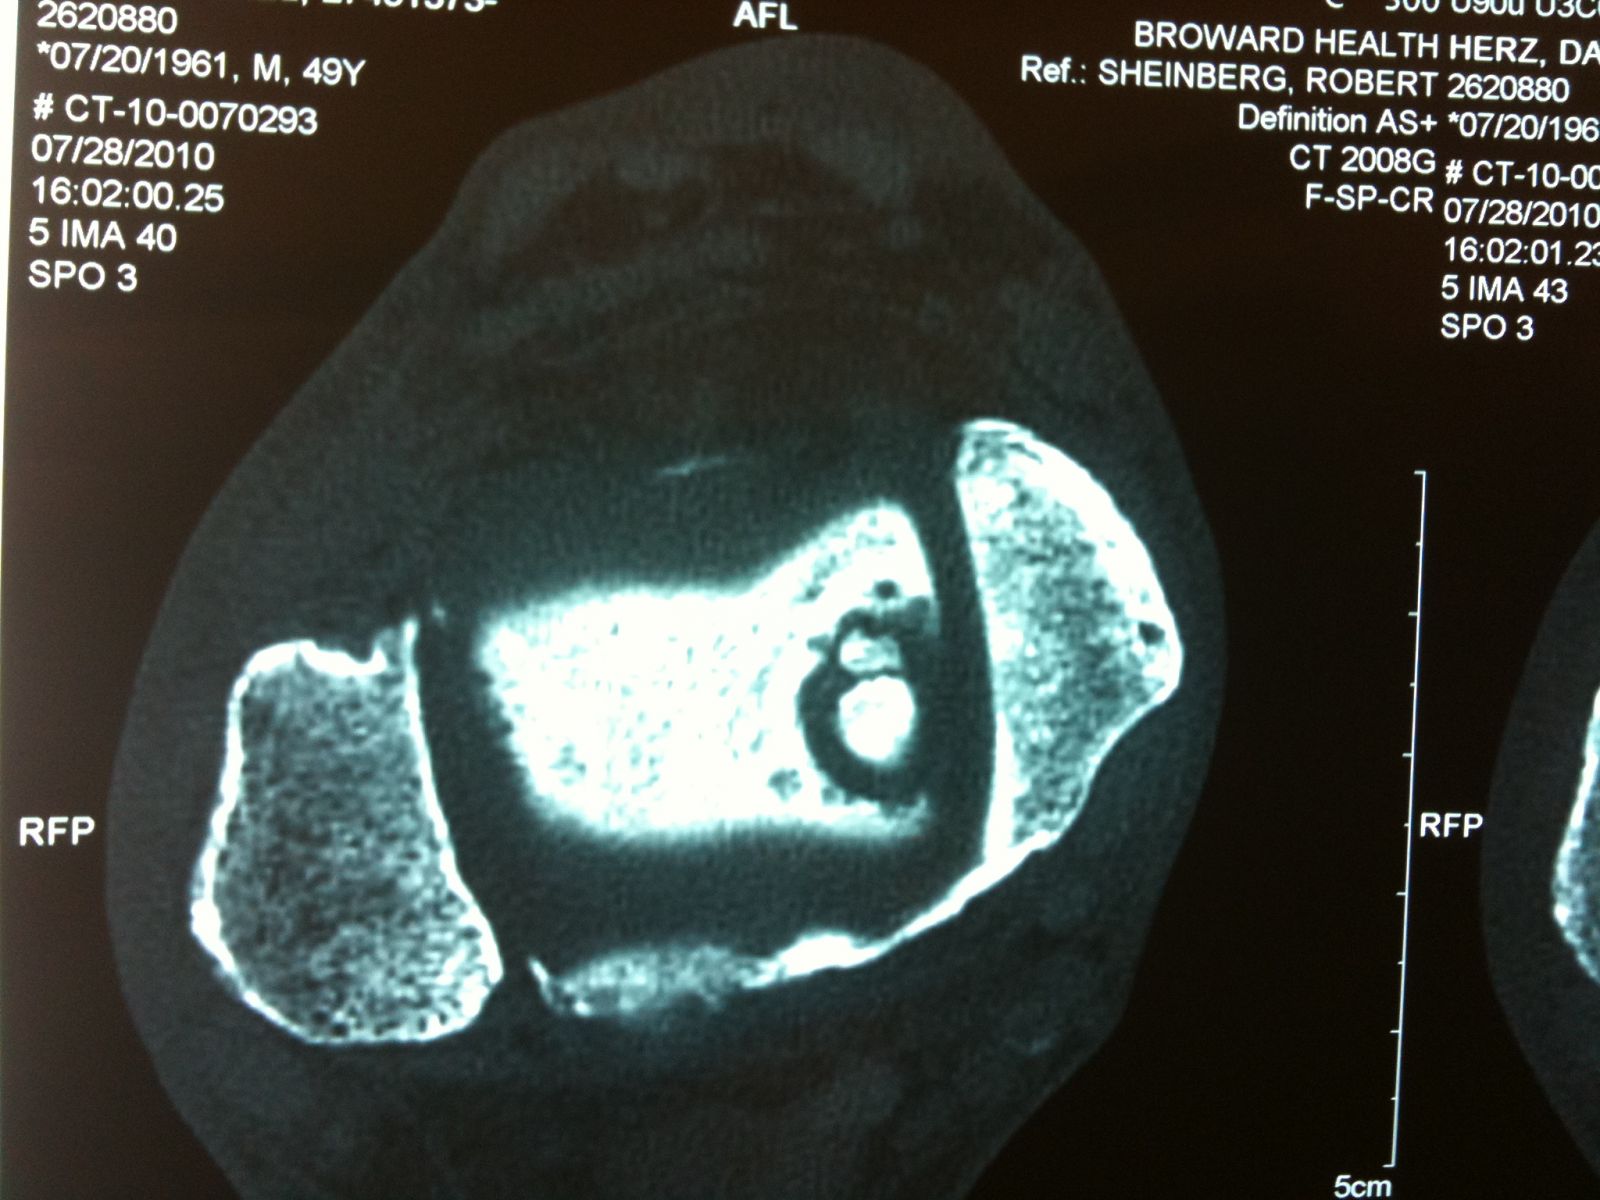

Intraop arthroscopic pics of talar OCD surgery.

A series of intraop ankle arthroscopy pics of synovial chondromatosis with OCD talus and tibia and microfracture.